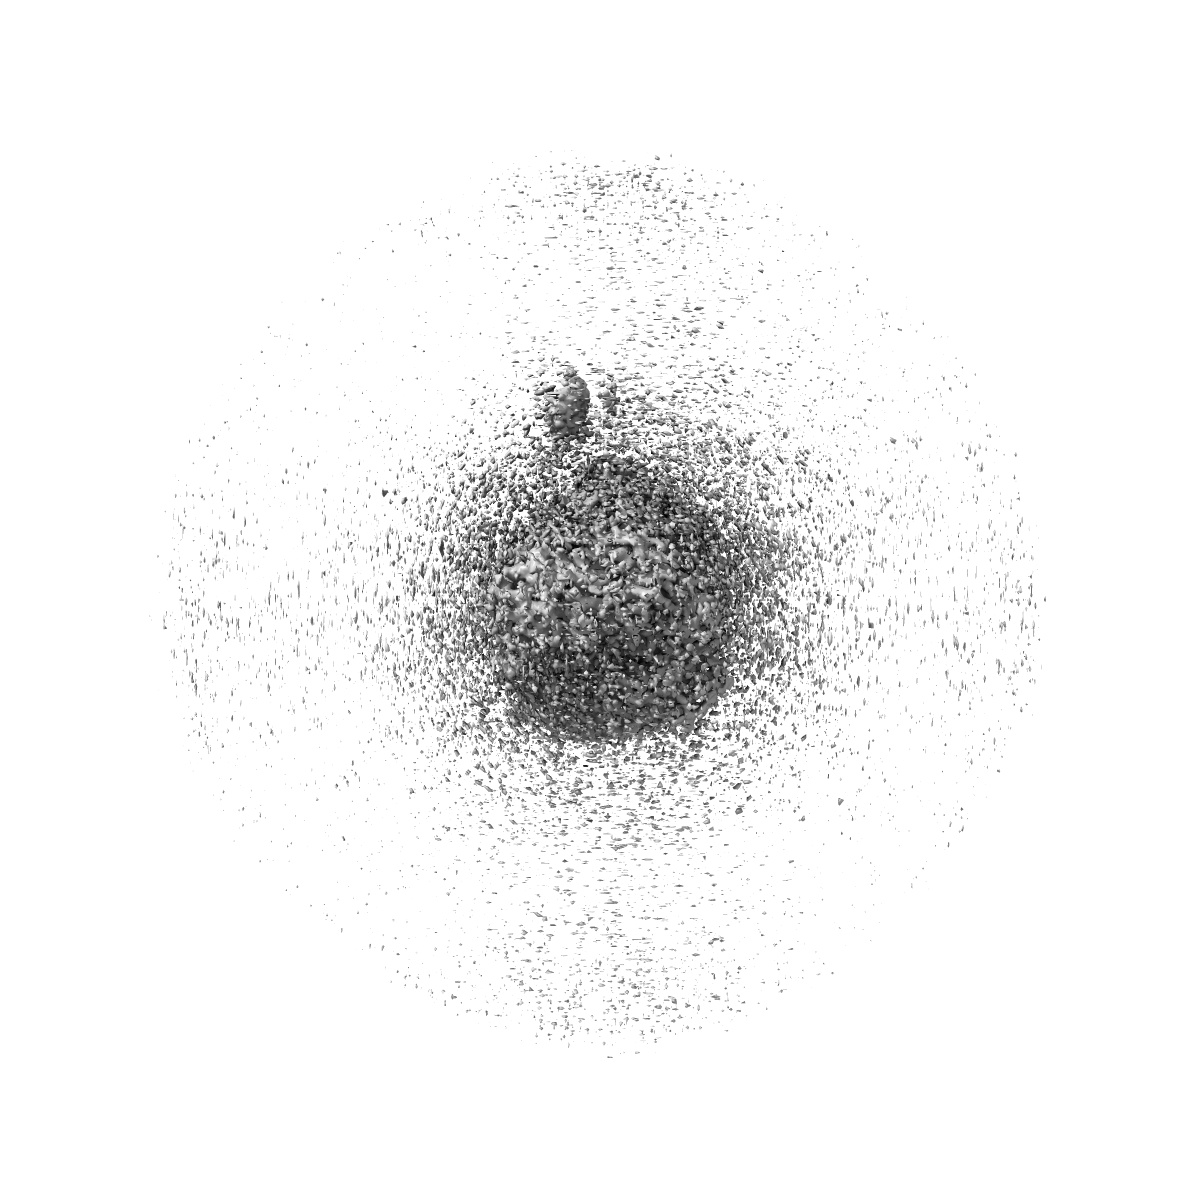

Cryo-EM structure of cancer-specific PI3Kalpha mutant E542K in complex with BYL-719

Single-particle2.77 Å

Sample: Human PI3Kalpha mutant E542K in complex with BYL-719